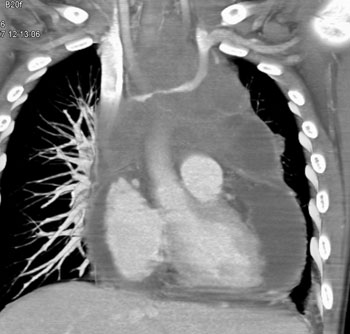

Question 14: HIV patient with increasing chest discomfort. The study was requested to rule out a pulmonary embolism. What is the diagnosis?

Diagnosis: Primary Cardiac Lymphoma and Pancreatic Mass

Tumor Involvement of the Heart and Pericardium in Lymphoma: Pathways of Involvement

• retrograde lymphatic extension

• hematogenous spread

• direct contiguous extension

• transvenous extension

Lymphoma Involves the Pericardium

Left Innominate Vein Encased